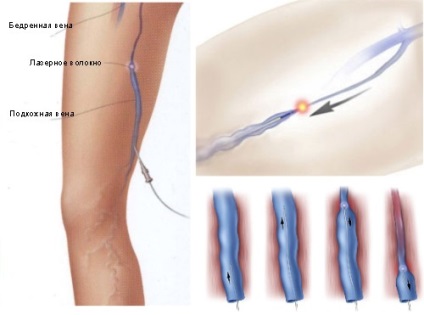

A második típus - az úgynevezett „zárt” műtét (endovénás véna termoobliteratsiya különféle energia). Egy sor ilyen műveletek EVLT - endovénás lézeres koaguláció vénák. Jelenleg ez a módszer a vezető a visszértágulatok kezelésében. Ellentétben nyitott sebészeti eljárás tart 20-60 percig, és nem igényel érzéstelenítést, nem vezet a fogyatékosság (ha a munka nem áll kapcsolatban a nehéz fizikai megterhelés), végezzük seb nélkül a bőrön helyi érzéstelenítésben történik.

A módszer azon a tényen alapul, hogy a módosított vénáról ultrahang hullámvezető keresztül van bevezetve, amely a lézersugár bécsi „zárt” belülről. A jövőben a 2-6 hónap, Vienna „megoldja”. Helyreállítása a vér normális áramlását fordul elő a műtőasztalon. A műtét után az alábbi korlátozások érvényesek: visel kompressziós harisnya (zokni) 3 hét, az első három napon, éjjel-nappal; restrikciós emelési gravitációs 10 kg 3 hét; tartózkodjon a szauna, fürdő és szolárium 2 hónap.